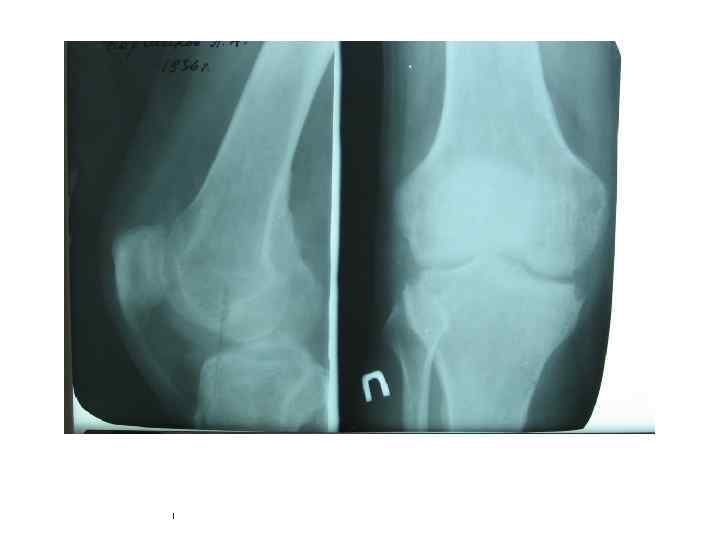

Туберкулезный гонит Туберкулёзные оститы эпифизов больше- и малоберцовой костей • прямая рентгенограмма; • компьютерная томограмма